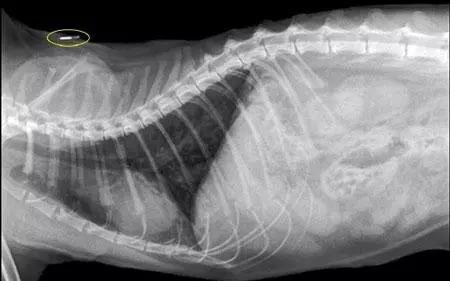

狗狗打芯片的意思是用注射器往狗狗的皮下注射芯片,芯片中带有全球唯一的身份识别码。狗植入芯片可以通过识别芯片信息知道狗狗的身份信息、犬主的信息,芯片还有定位的作用,在狗狗跑丢后可以及时找回。

芯片是一种以一定频率发射无线电波的装置,通常有三种不同的频率,芯片的形状是方形的,跟米粒的大小差不多具有一一对应的唯一性。芯片定向记录了宠物的基本信息,定位板的芯片还可以检测狗狗所在的位置。

芯片是植入到狗狗颈部附近的皮下,很难被发现,相当于狗狗的电子身份证,跟踪记载狗狗的情况,将作为宠物的电子身份证伴随其一生。

先匹配好狗狗的信息,检查芯片的ID号。在注射芯片前,把芯片阅读器放在针头上,确保读数清晰。这个数字会和狗狗的资料文件匹配,具有唯一的确定性。

固定狗后进行芯片注射,将芯片植入狗肩胛骨之间,轻轻地拉皮肤,直接在皮肤下敷贴。植入芯片对狗狗是没有任何不良影响的,也不需要酒精擦拭或采取其他措施。

芯片本身不是什么黑科技,注射的时候也不需要麻醉和开刀。大小就跟米粒差不多,长度约为0.8~0.9cm,通过注射器植入到宠物皮下,用专用扫描仪在狗狗身上一扫就能知道是否植过芯片了。宠物芯片被植入到宠物体内,极少有丢失的情况,对宠物健康也是安全的, 是管理宠物、增加找回机会的合适选择。